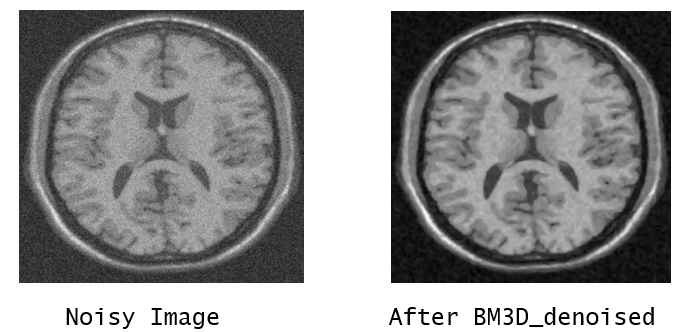

b. BM3D denoised – Block Matching and 3D filtering algorithm is a powerful tool for denoising the image with better results as compared to the other techniques. The suggested adaptive filtering technique’s self-adaptation and stability have allowed it to achieve excellent noise reduction performance while preserving high spatial frequency information. We have used all the stages as most of the stage arguments have hard thresholding.

Refer to caption

Figure 5:

The best result which is obtained by BM3D denoising is used for further process.